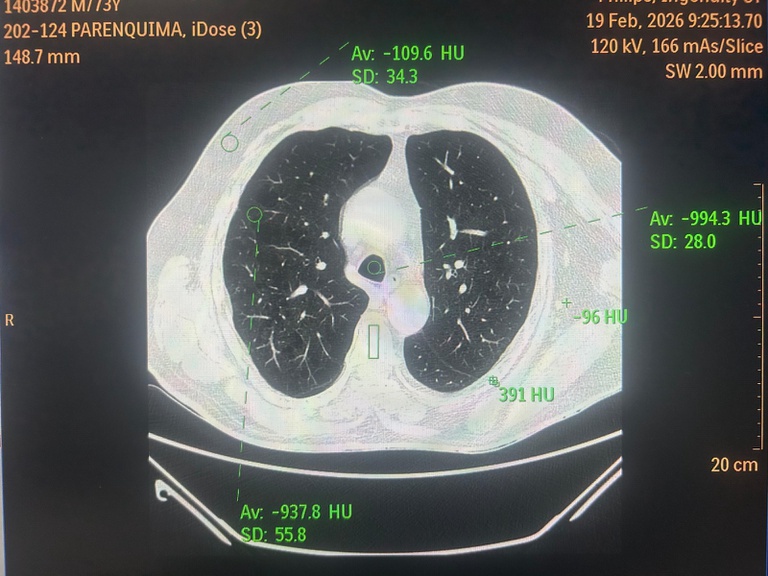

24022026 ebserh huuac-ufcg físico médico 3.jpeg

Profissional supervisiona práticas de segurança como avaliação de blindagem das salas de exames, análise de protocolos e verificação do cumprimento das normas regulatórias vigentes. Foto: Jamerson Albuquerque Júnior.

De acordo com o físico médico do Hospital Universitário Alcides Carneiro (HUAC-UFCG), Jamerson Albuquerque Júnior, a atuação vai muito além da verificação técnica dos equipamentos. “Nosso trabalho é garantir que a tecnologia esteja realmente a serviço do paciente. Realizamos testes de desempenho, calibrações e avaliações técnicas periódicas para assegurar que a imagem tenha qualidade diagnóstica e que a dose de radiação utilizada seja a menor possível, sempre dentro dos níveis de segurança recomendados”, explica.

Entre as principais atribuições está o controle de qualidade clínico dos exames. Na tomografia, por exemplo, o profissional avalia parâmetros como nível de ruído, resolução espacial e resolução de contraste, ajustando fatores técnicos como corrente do tubo, espessura de corte e algoritmos de reconstrução. O objetivo é equilibrar qualidade de imagem e proteção radiológica. “Não avaliamos apenas o equipamento, mas o resultado que chega ao médico radiologista,” destaca o especialista.